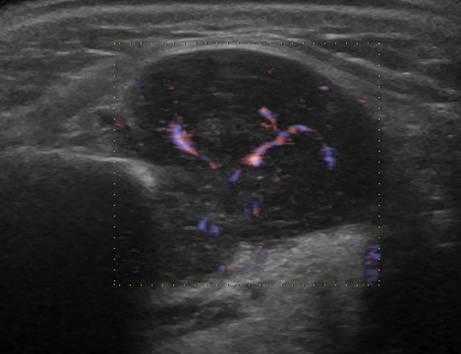

U tuyến nước bọt

» Thông tin: Nam giới – 63 tuổi.

» Lâm sàng: Khối vùng góc hàm.

# Lymphoma tuyến nước bọt dưới hàm.